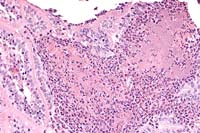

Case 23-2. Intestine. Focal mucosal necrosis with a myriad of ill-defined bacteria appearing as a basopilic haze, surrounded by neutrophils. 20X

AFIP Diagnosis: Small intestine: Enteritis, necrotizing, neutrophilic, acute, multifocal, moderate, with crypt abscesses, transmural edema, and bacterial colonies, Jersey, bovine.

Conference Note: Yersinia pseudotuberculosis (YP) is a gram-negative coccobacillus which causes disease in a wide range of animal species, including birds, rodents, carnivores, cattle, sheep, goats, captive exotic ungulates, nonhuman primates and man.3 In man and nonhuman primates, YP causes a necrotizing, ulcerative enteritis, sometimes with mesenteric lymphadenitis.3,5 The most frequently seen form of disease in birds, rodents, and carnivores is a septicemia leading to localization of the organism in liver and spleen, with extensive caseating abscesses.3 Enterocolitis, and rarely abortion, have been reported in cattle, sheep, and goats. Yersiniosis in domestic animals is most significant in Australia and New Zealand, where it is a reported cause of disease in sheep, cattle, goats, deer and pigs.4

In all affected animal species, lesions in subacute to chronic yersiniosis may be mild, and are usually limited to watery intestinal content, with congestion, edema, small focal hemorrhages, or mild erosion and ulceration of the intestinal mucosa. In the colon, raised nodules with depressed centers may be seen, and mesenteric lymph nodes are often enlarged, congested, and edematous. Multifocal hepatic necrosis is sometimes a feature. In fulminant infections, there is a fibrinous or fibrinohemorrhagic enterocolitis, with mucosal colonization by large masses of coccobacilli and a marked influx of neutrophils.